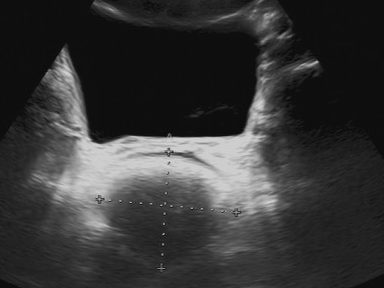

Ultraschall der Nieren

Wir empfehlen allen Eltern eine Ultraschalluntersuchung der Nieren ihres Neugeborenen.

Fehlbildungen der Nieren zählen zu den häufigsten angeborenen Veränderungen und lassen sich durch eine frühzeitige Untersuchung zuverlässig erkennen.